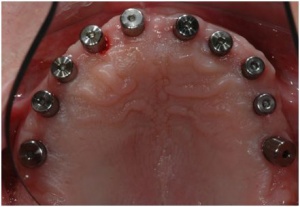

Il s'agit de la réalisation prothétique de deux bridges complets maxillaire et mandibulaire sur implants dont la phase chirurgicale est actuellemnt sur le site en vidéo.

-la mise en charge des implants